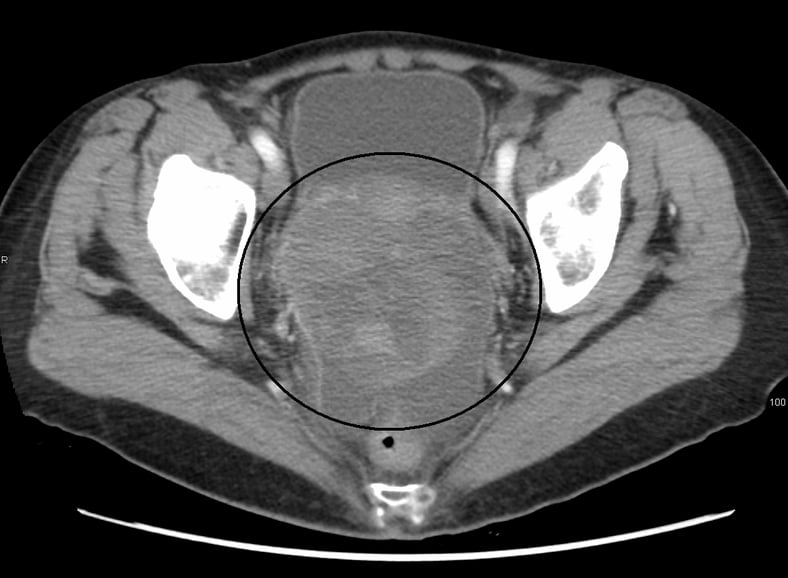

Only about 20% of ovarian cancers are detected at an early stage, as there has yet to be a screening or test developed to screen for early treatment, according to Dr Wong Yen Shi of SMCV.

“Transvaginal scans and CA 125 tumour marker tests are used to detect it, but these have limitations. Scans can detect masses, but it can be difficult to differentiate a benign tumour from a malignant one, while marker tests are good for monitoring treatment but not so much for screening.”

She said ovarian cancer symptoms include bloating, abdominal discomfort, urinary frequency, constipation, feeling full quickly, loss of weight, fatigue, and back pain. This cancer can be mistaken for benign ovarian tumours, uterine fibroids, endometriosis, and premenstrual syndromes.